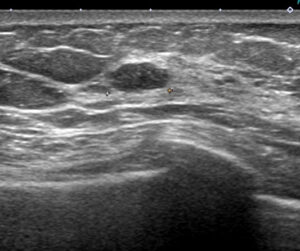

これが検診時の画像

私カテゴリーでは「私cat.6 乳癌の可能性がかなり高い」

例)スピキュラはないけど不整形、境界不明瞭

♯ちなみに一般的なカテゴリー(1~5)では4となります。